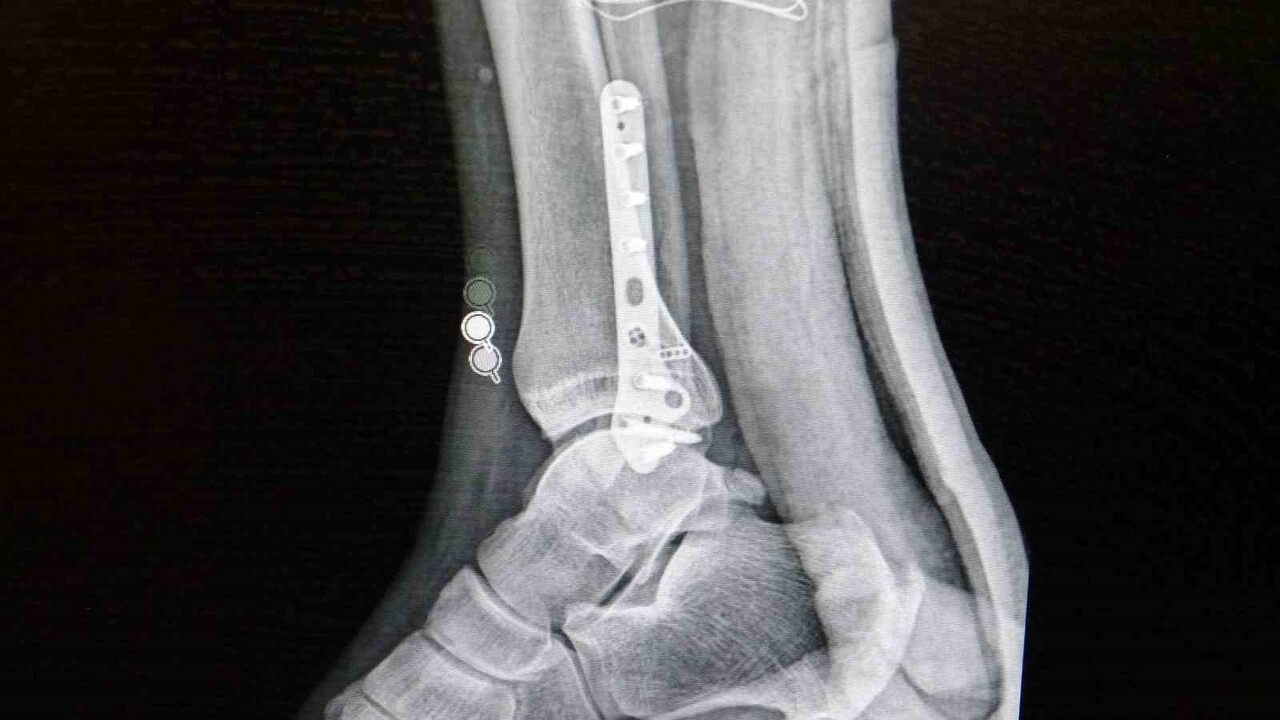

Ortopedi polikliniklerine en sık başvuran yaralanmaların ayak bileği, diz ve omuzda olduğunu belirten Demirbaş, futbolun yaralanma oranlarının en yüksek olduğu branşlardan biri olduğunu ifade etti. Bu bağlamda, menisküs yırtıkları, ön çapraz bağ yırtıkları ve aşil tendon kopmalarının sık görüldüğünü söyledi.